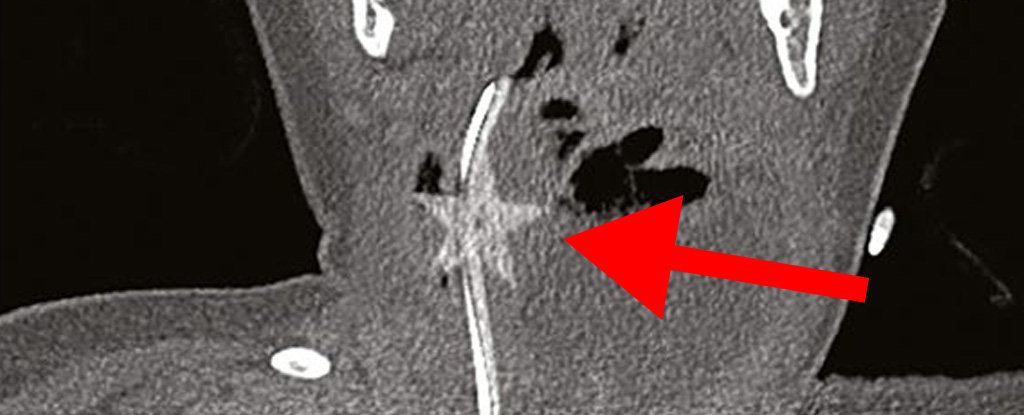

ScienceTechyNews: Terrifying Medical Case Shows Why You Should Be Wary of Confetti Stars This Christmas